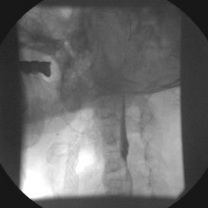

Fig. 27. A.Stenoză de arteră carotidă internă stângă B. După implantare de

stent autoexpandabil (Wallstent)

Fig. 28. A. Stenoza de arteră carotidă internă dreaptă B. După implantare de stent autoexpandabil flexibil (Smart).